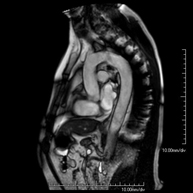

Prova diagnòstica no invasiva que consisteix en l'obtenció d'imatges d'alta definició anatòmica de l'abdomen mitjançant l'ús d'un camp electromagnètic i ones de ràdio (amb un emissor i un receptor). No utilitza radiació ionitzant. En aquesta exploració s'inclouen el fetge, el pàncrees, la melsa, la via biliar, la vesícula biliar, les glàndules suprarenals, els ronyons, l'aorta abdominal, la vena cava inferior, l'estómac, el duodè, etc. En alguns casos caldrà emprar contrast paramagnètic (Gadolini) per caracteritzar les lesions. - RM Pelvis femenina

Prova diagnòstica no invasiva que consisteix en l'obtenció d'imatges d'alta definició anatòmica de la pelvis mitjançant l'ús d'un camp electromagnètic i ones de ràdio (amb un emissor i un receptor). No utilitza radiació ionitzant. Es realitza per a l'estudi de patologies d'úter, d'ovari, de trompes i de vagina, ja siguin d'origen tumoral, inflamatori o vascular. També permet valorar les estructures adjacents localitzades a la pelvis i la identificació de les seves alteracions. De vegades és necessari l'ús de contrast intravenós (Gadolini) per caracteritzar les lesions. - RM Pelvis masculina